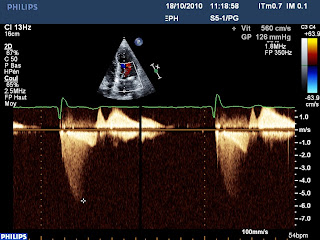

Pourtant il ne s’agit ni d’une thrombose de bioprothèse (au demeurant très rare en position aortique), ni d’une disproportion patient prothèse, mais d’un SAM (systolic anterior motion) de la grande valve mitrale, qui se replie dans la chambre de chasse du VG, ce qui engendre un obstacle sous aortique (Cf photo Doppler couleur) et une insuffisance mitrale :

En Doppler continue, on peut obtenir le flux d’IM et celui d’obstacle intra ventriculaire gauche sur la même image :